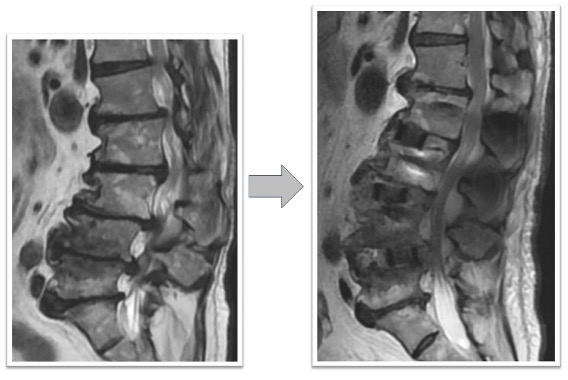

椎間板ヘルニア(図1)

体動困難を伴う激烈な下肢痛に対してL4/5の固定術を実施。術前に認められていたL4/5の椎間板ヘルニアがOLIFによる固定術後、間接除圧効果などによって消失しています(図1、赤丸)。レントゲンでは椎間ケージと腰椎L4とL5を固定する椎弓根スクリューが確認できます(図1、下段)。本症例の傷は左わき腹に4-5cmと、背部のスクリュー刺入部位に2㎝弱の傷が4つとなります。術後、痛みは消失しました。

図1